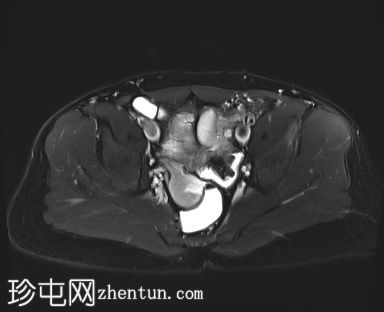

MRI

轴位

STIR

8.jpg

MRI图像显示子宫和睾丸。子宫内膜腔开口于前列腺尿道。

患者有双侧隐睾病史。CT和MRI图像显示发育良好的子宫和两个睾丸,均位于盆腔内。子宫内膜腔开口于前列腺尿道。